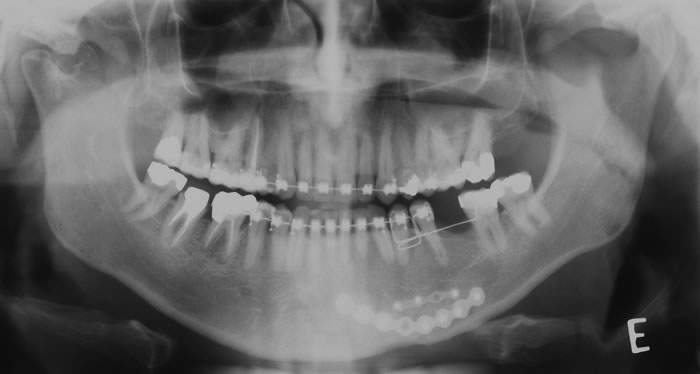

CASO 3 - Fratura de ATM

Paciente com história clínica de trauma. Fratura no côndilo direito com deslocamento do fragmento para medial e deslogamento do côndilo para lateral da cavidade articular.